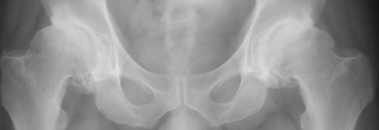

[Ortho] Двусторонний коксартроз 1

На консультации пациент, 47 лет. Жалобы на ограничение движений в тазобедренных суставах, возникшие 1,5 года назад. Около года назад появились боли справа. Лечился консервативно. С незначительным эффектом. Рефмеханик, до последнего времени ходил в море.   Анализы – норма. Объективно: утиная походка, ограничение сгибания в тазобедренных суставах до 90 градусов. Ротация отсутствует. Отведение ограничено незначительно.

Хотелось-бы услышать мнения по лечению, в частности - имеют-ли смысл операции не эндопротезирования?